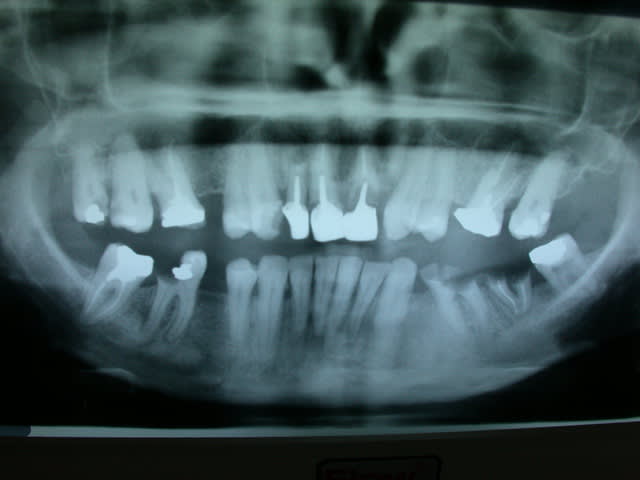

radich_a_tord

A moi

JF la trentaine...